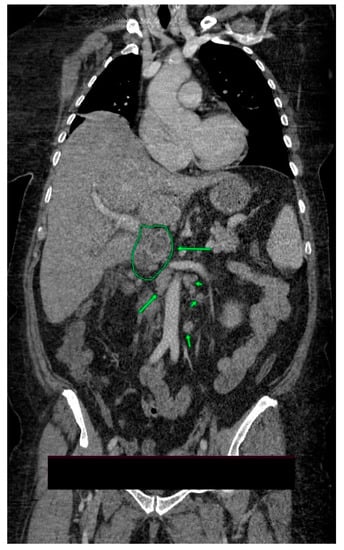

2. Case Presentation